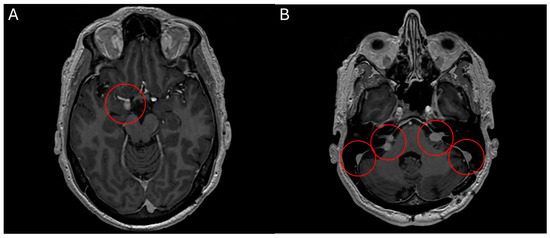

Figure 5.

MRI head scan, 25 March 2024, before commencement of treatment with belzutifan: multiple CNS parasellar haemangioblastomas (A) and cerebellopontine angle (B).

Figure 6.

MRI head scan, 5 July 2024, after 10 weeks treatment with belzutifan: regression of CNS parasellar haemangioblastomas (A) and cerebellopontine angle (B).

2.4. Belzutifan in Haemangioblastomatosis

Case 5 A 60-year-old male patient presented with a symptomatic, solitary cerebellar HB. Surgical resection was performed with complete remission of neurological symptoms. A multimodal clinical evaluation did not reveal any evidence for VHL-disease. Clinically, he presents with disseminated haemangioblastomatosis. A somatic VHL mutation was repeatedly detected in resected specimens by molecular genetics. However, no germline mutation could be found. The first surgical intervention was performed in 2015 with the removal of a cerebellar HB. In the following years, various other resections of HBs were performed in the cranial and spinal regions. There have been no further manifestations to date. The present disseminated haemangioblastomatosis is considered an ultra-rare disease. Accordingly, there are no standard treatments, or evidence-based therapeutic recommendations that go beyond individual case reports. MR staging from May 2023 showed disease progression, both cerebrally and spinally. Most intracranial HBs were progressive in size, the largest of which was medially adjacent to the right amygdala region with progressive perifocal oedema. The vertebrospinal region also showed a progression in size in most known HBs (most prominent finding at the level of C3/4). Clinically, the patient reported mild headaches and neck pain, as well as mild ataxia, which had already existed in previous years and was not newly aggravated. An application for cost approval for belzutifan was rejected by the health insurance company in 2023. Following case reports, the VEGF inhibitor bevacizumab was administered in three weekly doses from mid-2023. After four cycles of bevacizumab, disease progression was initially halted. Unfortunately, a multilocular asymptomatic progression in the number and size of the intracranial and spinal HBs occurred as early as December 2023. Subsequently, the treatment interval with bevacizumab was intensified and shortened to 2 weeks. The patient also reported significantly worse hearing on the left side from the end of 2023, this hearing loss could also be objectified in an audiometry and was most likely due to compression of the auditory nerve on the left side by a growing HB. However, an MR restaging from March 2024 revealed further disease progression. Treatment with belzutifan was finally started in April 2024 after obtaining reimbursement. After about 10 weeks, belzutifan showed a substantial response in all cerebral and spinal findings. In some cases, the HBs almost halved in size (Figure 5 and Figure 6). The patient also benefited greatly from the treatment, subjectively. His hearing in his left ear improved noticeably within 4 weeks of starting treatment with belzutifan. He can now use his left ear to make a phone call again. In the meantime, his balance has also improved, and the patient is able to ride a bicycle again. From June, the patient developed mild anaemia under belzutifan (haemoglobin 120 g/L), asymptomatic for the patient. The current MRI again shows low size regression of isolated spinal HBs. The intracranial HBs are stable in size. Furthermore, no new spinal or intracranial HBs have occurred. Due to the ongoing response to treatment, both MRI graphically and subjectively, treatment is currently being continued unchanged with 120 mg belzutifan daily.